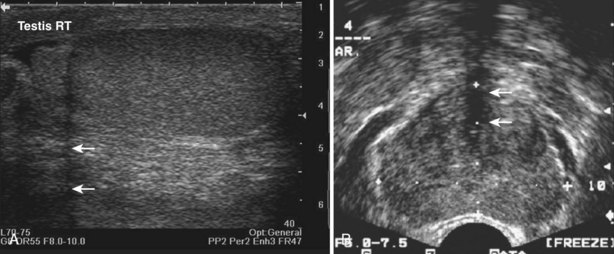

When interacting sound waves are in phase or out of phase, their amplitude will be enhanced or diminished. This pattern of interference is partially responsible for the echo architecture or texture of organs. One pattern of interference, commonly called “speckling” (Fig. 4–19), is seen in organs with fine, internal histology such as the testis.

Figure 4–19 Fine internal echogenicity called “speckle” is caused by scattering of sound waves and the resultant pattern of interference. Note the resulting finely granular, homogenous echogenicity (arrows) of the testicular parenchyma.